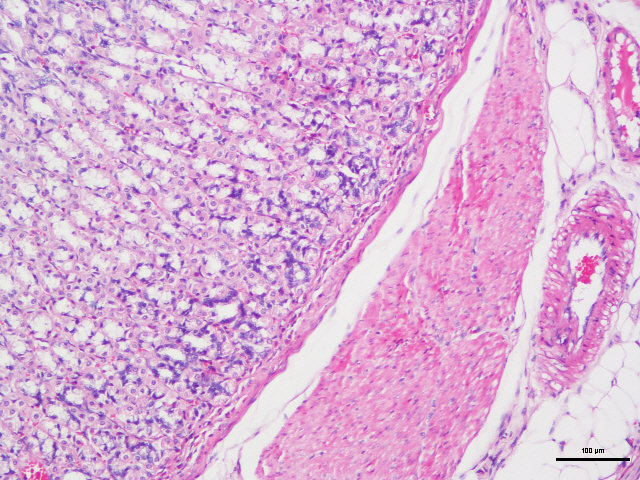

病理学的所有切片,都必须通过一种以上的染料,通过各种不同的方法,将切片中各种不同的物质,在不同染液的作用下,将其显示出来,使之在光学显微镜下,能够完全的观看各种结构。例如,HE染色,好质量的切片可以清晰地显示出许多不同的结构,细胞核着蓝黑色,细胞浆着粉红色,软骨着蓝色等。清晰的结构为诊断提供可靠的依据,因此,染色技术也是病理技术中的重要组成部分,必须不断地总结,方能提高。如果染色不好,切片染色一团糟,红蓝不分,结构不清,层次不明,影响了镜下的观察,直接影响了临床诊断,染色结果的好坏直接关系到诊断的准确性。

(25)中性树胶封固。结果:细胞核被染成深蓝黑色;细胞浆被染成粉红色;软骨及钙盐被染成蓝色;胶原纤维染成淡粉红色,嗜酸性细胞及嗜酸性颗粒呈鲜红色;弹力纤维呈淡粉红色;某些蛋白性物呈粉红色等。

样片参考:

肠

鼻粘膜

肺

肝

肌肉横截面

脑

胃

心脏

子宫

细胞

HE染色 | 染色含切片 | 苏木.精-伊红染色法,观察组织形态 |